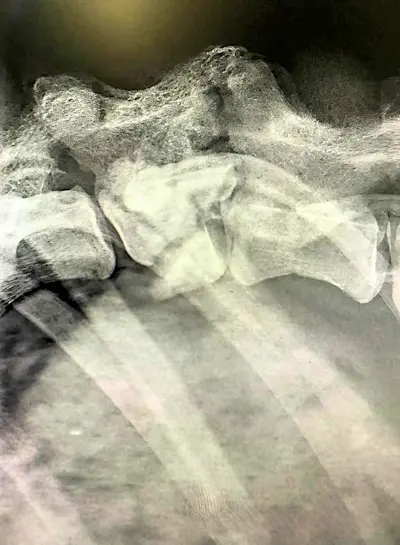

Endlich war es soweit und Lordina konnte am 24.04.24 zum Röntgen in die Klinik gebracht werden.

Die Bilder erbrachten einen eindeutigen Befund: die Wirbelsäule von Lordina ist gebrochen.

Es grenzt also an ein Wunder, dass wichtige Nerven nicht schwer verletzt bzw. durchtrennt wurden und sich Lordina nach dem schweren Trauma durch die kompetente Behandlung der Tierärzte im rifugio wieder soweit erholen konnte, dass sie zumindest selbständig gehen kann.

Für den weiteren Verlauf bedeutet dies, dass sich Lordina nun auch die nächsten Wochen nicht viel bewegen darf, also solange, bis sich ausreichend Kallus gebildet und sich die Wirbelsäule in ihrer jetzigen Position dadurch gefestigt hat. Eine Operation wird nicht notwendig sein.